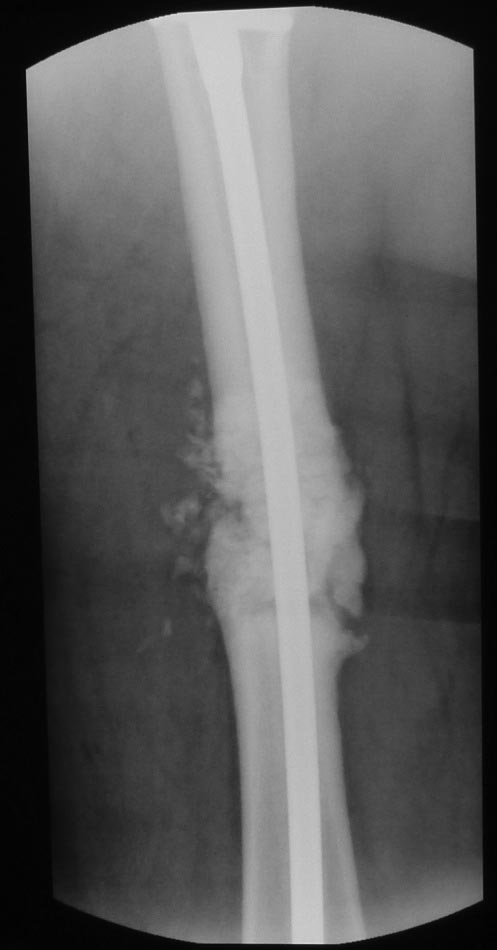

Уважаемые коллеги. Хотелось бы выслушать мнения и советы по представленному случаю. Пациент 42 лет, вес 130 кг, рост около 160 см, сахарный диабет в легкой форме (впервые выявлен после травмы). Травма в феврале 2011 г. - упал с мотоцикла на отдыхе за рубежом. По возвращении в Россию был прооперирован в несколько этапов: в марте 2011 г. - остеосинтез обеих костей правого предплечья пластинами по поводу открытого перелома; интрамедуллярный остеосинтез правого бедра; остеосинтез проксимального конца правой большеберцовой кости. В апреле 2011 г. был доставлен 1 блокирующий винт в дистальное отверстие гвоздя и выполнена пластика крестообразных и наружной боковой связок левого коленного сустава. В феврале 2012 г. были удалены фиксаторы с проксимального конца правой большеберцовой кости и выполнена пластика крестообразных и наружной боковой связок правого коленного сустава. За это время пациент смог начать ходить, сначала с костылями, а затем - без дополнительной опоры. Летом 2013 г. решил укрепить ноги с помощью подъемов пешком на пятый этаж. В результате - усталостная рефрактура правого бедра и перелом интрамедуллярного гвоздя. 09.09.2013 - реостеосинтез латеральным бедренным гвоздем с пластикой костной аутостружкой + СhronoS. Сейчас, через 6 мес после операции, может ходить без дополнительной опоры, периодически беспокоит болезненность в области правого бедра. На сегодняшних КТ - отсутствие признаков консолидации. Нужно ли что то делать и, если да, то что? Рассматриваемые варианты: повторная костная пластика дефекта; доставить блокирующие винты (самый проксимальный винт был удален через 3 мес после операции). Еще раз менять гвоздь не хотелось бы. На представленных снимках: бедро в 2011 г., через несколько мес после операции; в 2012 г., на стадии консолидации; со сломанным гвоздем; сразу после повторной операции (3 рентгенограммы). Все КТ - сегодняшние. Заранее спасибо за ответы.

Доброго дня! Уважаемый Сергей, думаю, что проблема не в необходимости костной пластики, а в отсутствии стабильной фиксации (как при инфраистмальном переломе большеберцовой кости).

ждать-не ждать? Срочности нет, подождать можно, но активно, т.е. оценить клиническую и рентгенологическую динамику: два месяца назад, сейчас и еще через пару месяцев. Уменьшатся боли, появится более убедительная мозоль - ждите и наблюдайте дальше. Отсутствие положительной динамики можно приравнять к отрицательной динамике. Очевидно, что здесь имеют место быть обе проблемы: биологическая -мозоль слабая и механическая - тонкий гвоздь, недостаточная стабильность. Тогда -удаление, рассверливание (очень аккуратное, по 0.5 мм шаг, острыми фрезами, чтобы не пожечь кость - кортикал толстый и довольно прочный). Для 130 кг диаметр гвоздя минимум 12 мм, лучше больше. Здесь можно и 14мм гвоздь взять и блокировать дистально винтами 6,0 мм. Открывать перелом и пытаться делать еще пластику экстрамедуллярно не стоит. Рассверливания будет достаточно.

Источник проблем - отсуствие рассверливания, тонкий гвоздь и костная пластика. При интрамедуллярном остеосинтезе (относительная стабильность) класть кусочки кости открыто бесполезно - не приживут. Только еще ухудшили кровоснабжение концов. А что там с длиной сегмента? Если длина не потерялась - реостеосинтез с рассверливанием, как А.Семенистый написал. Если укорочение - удалить, остеотомия на другом уровне и дистракиця, на стыке - компрессия, и по достижении нужной длины - заштифтовать с рассверливанием, аппарат снять только после запирания гвоздя.

Боли в области ложного сустава подтверждают, что ожидания не помогут и приведут к повторному перелому интрамедуллярного гвоздя. Стандартная процедура - рассверливание и толстый гвоздь в динамике. Нагрузка с первых дней.

Прежде все го - исключите инфекцию. Много предрасполагающих факторов: вес, несколько вмешательств, нестабильность на фоне перелома фиксатора, сахарный диабет, какая-то серома.